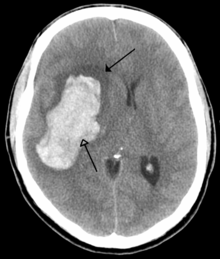

The main risk factor for stroke is high blood pressure.[4] Other risk factors include tobacco smoking, obesity, high blood cholesterol, diabetes mellitus, previous TIA, and atrial fibrillation.[2][4] An ischemic stroke is typically caused by blockage of a blood vessel.[5] A hemorrhagic stroke is caused by bleeding either directly into the brain or into the space surrounding the brain.[5][6] Bleeding may occur due to a brain aneurysm.[5] Diagnosis is typically with medical imaging such as a computerized axial tomography (CT) scan or magnetic resonance imaging (MRI) scan along with a physical exam. Other tests such as an electrocardiogram (ECG) and blood tests are done to determine risk factors and rule out other possible causes. Low blood sugar may cause similar symptoms.[7]

Intracerebral hemorrhage

It generally occurs in small arteries or arterioles and is commonly due to hypertension,[40] intracranial vascular malformations (including cavernous angiomas or arteriovenous malformations), cerebral amyloid angiopathy, or infarcts into which secondary hemorrhage has occurred.[2] Other potential causes are trauma, bleeding disorders, amyloid angiopathy, illicit drug use (e.g., amphetamines or cocaine). The hematoma enlarges until pressure from surrounding tissue limits its growth, or until it decompresses by emptying into the ventricular system, CSF or the pial surface. A third of intracerebral bleed is into the brain's ventricles. ICH has a mortality rate of 44 percent after 30 days, higher than ischemic stroke or subarachnoid hemorrhage (which technically may also be classified as a type of stroke[2]).

Hemorrhagic strokes and are classified based on their underlying pathology. Some examples of hemorrhagic stroke are hypertensive hemorrhage, ruptured aneurysm, ruptured AV fistula, transformation of prior ischemic infarction, and drug induced bleeding.[50] They result in tissue injury by causing compression of tissue from an expanding hematoma or hematomas. This can distort and injure tissue. In addition, the pressure may lead to a loss of blood supply to affected tissue with resulting infarction, and the blood released by brain hemorrhage appears to have direct toxic effects on brain tissue and vasculature.[35][51] Inflammation contributes to the secondary brain injury after hemorrhage.[51]